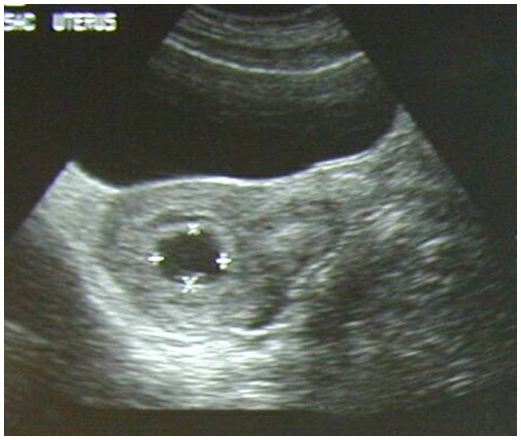

Normal Intrauterine Pregnancy